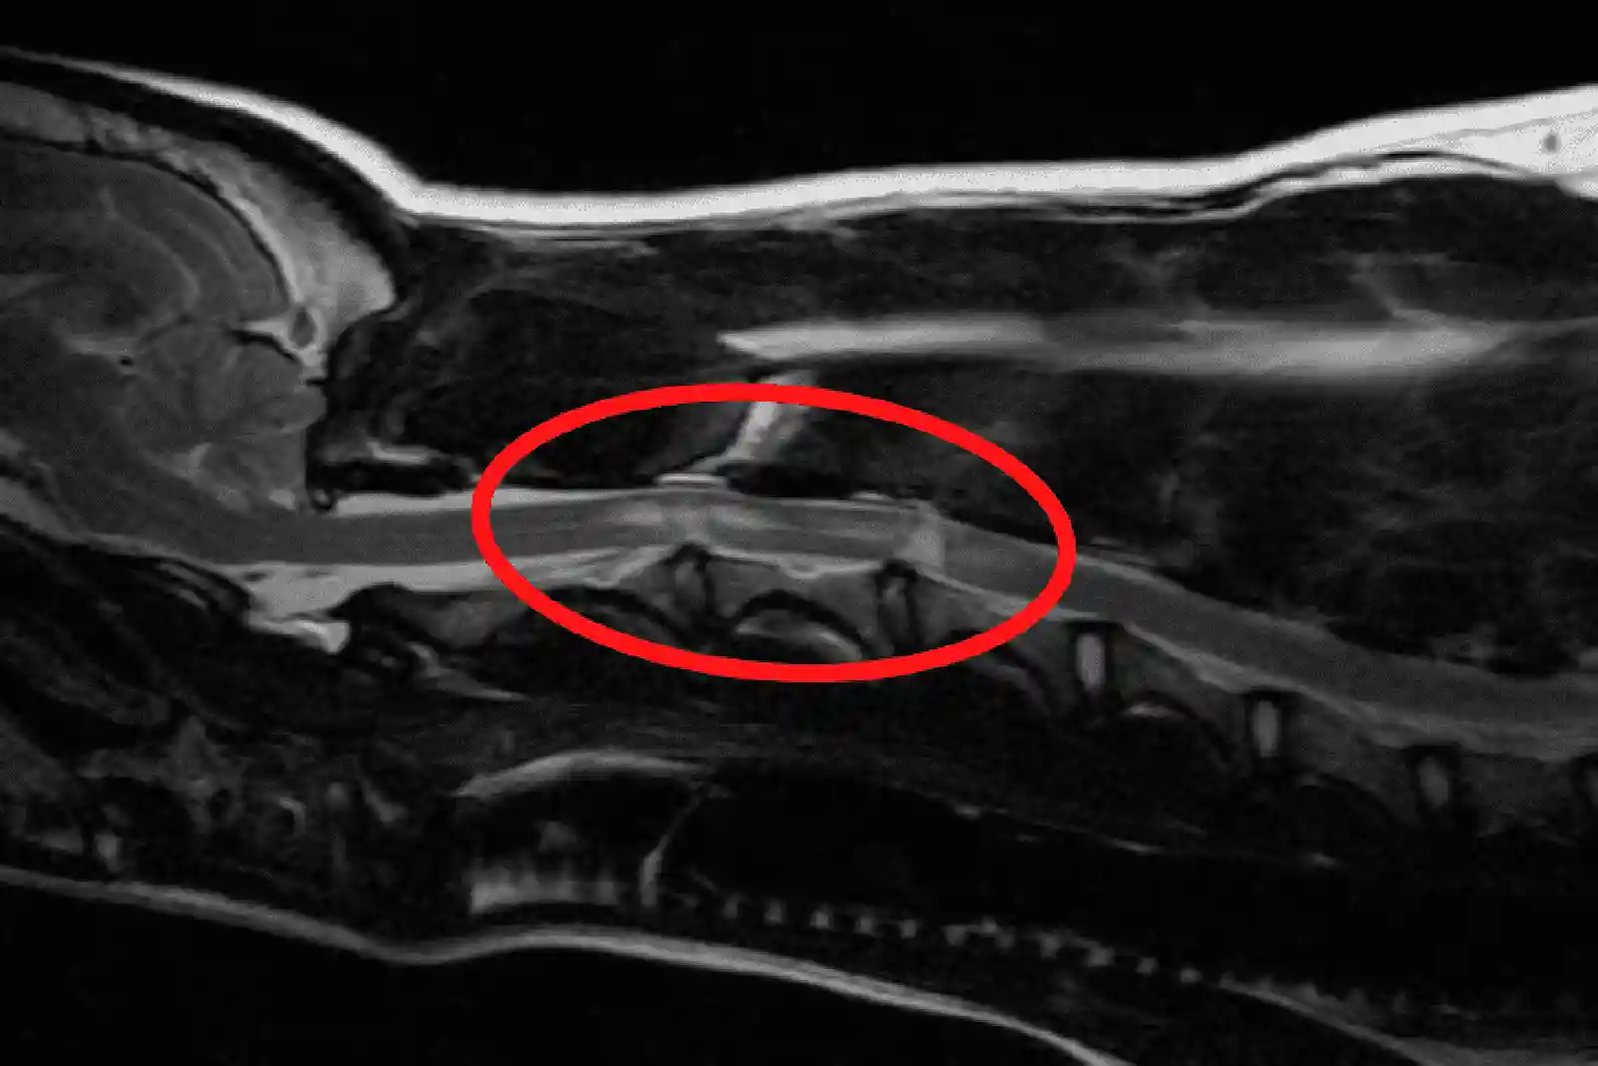

Todas as formas de doença do disco intervertebral em cães exigem exames de imagem avançados para o diagnóstico definitivo. A ressonância magnética é considerada o padrão ouro, pois pode distinguir entre compressão, obstrução, contusão e tumor. A RM também pode ajudar a prever o prognóstico, com base no tamanho da área afetada e na gravidade do dano.

Os critérios da RM para diagnosticar uma extrusão aguda não compressiva do núcleo pulposo em cães são

- Lesão hiperintensa acima do disco

- Volume reduzido do núcleo pulposo do disco

- Pequeno volume de material extradural acima do disco

- Estreitamento do espaço do disco

- Sem compressão da medula espinhal